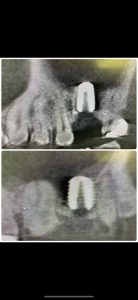

朝より、ソケットリフト

患者さんの希望により左右同時に!

非常に侵襲が少ない術式だからオッケー👌

異物は一切入れないデンサーリフト!

難なく40分で終わり、値も良く6w後には仮歯

印象予定